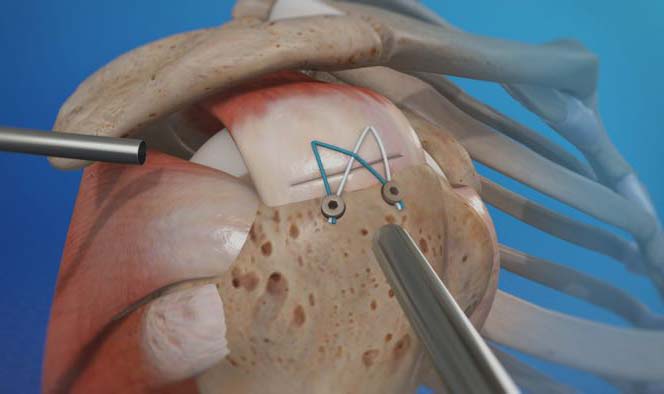

Arthroscopic Rotator Cuff Repair

For a less invasive option, Melbourne Orthopaedic Clinic offers arthroscopic rotator cuff repair. This technique uses small incisions and an arthroscope (a tiny camera) to guide the surgery, allowing the surgeon to view the joint in high definition on a monitor. Arthroscopic surgery minimises tissue damage, reduces recovery time, and promotes a faster rehabilitation process, making it ideal for most cases of rotator cuff injury.